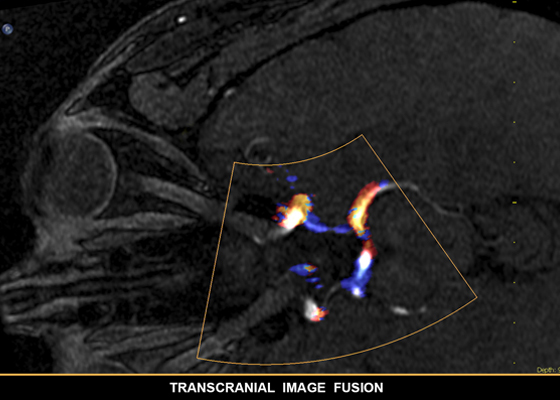

EchoNavigator, unione di immagini radiologiche ed ecografiche in tempo reale

Informazioni migliori e maggiore affidabilità per l'individuazione del problema e la sua soluzione con SmartFusion. EchoNavigator unisce automaticamente le immagini Live 3D TEE e le immagini radiografiche in tempo reale consentendo una guida intuitiva e rapida del dispositivo nello spazio 3D.